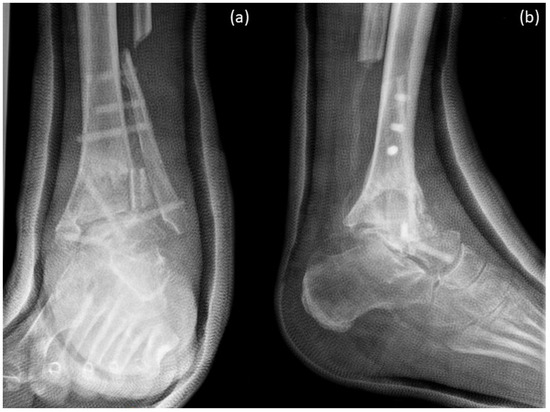

Arthrodesis and Defect Bridging of the Upper Ankle Joint with Allograft Bone Chips and Allograft Cortical Bone Screws (Shark Screw®) after Removal of the Salto-Prosthesis in a Multimorbidity Patient: A Case Report

2. Case Presentation

3. Surgical Procedure